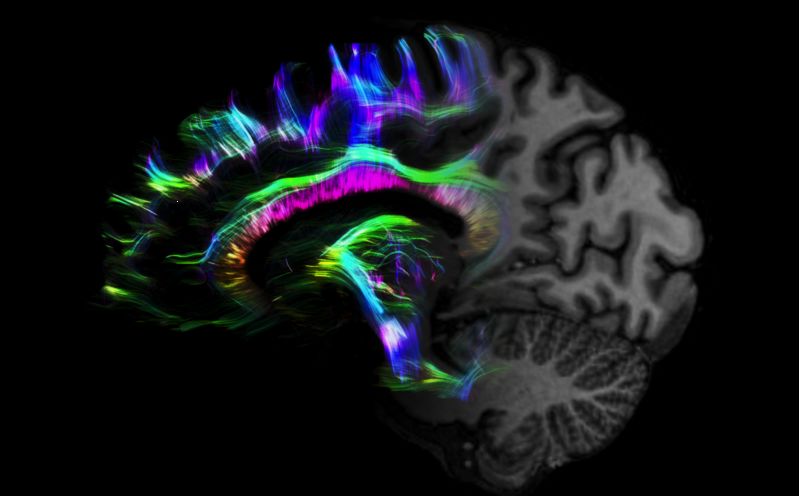

1毫米的各向同性分辨率DTI:神經(jīng)纖維束的交叉細(xì)節(jié)顯示

0.8毫米的各向同性分辨率:精確劃分灰質(zhì)和白質(zhì)